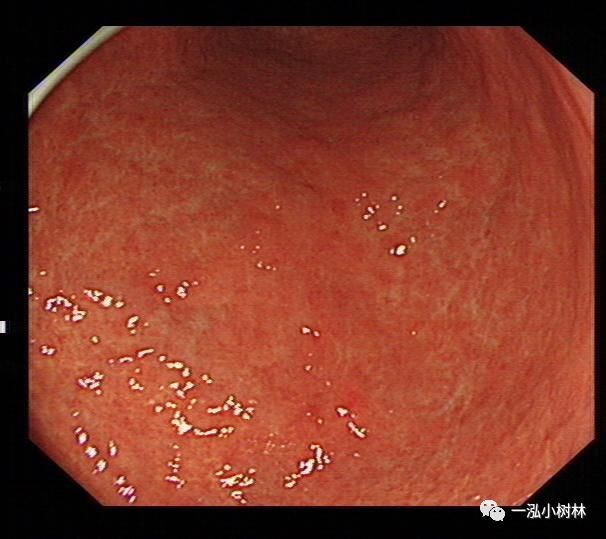

萎缩性胃炎普通内镜表现:黏膜苍白,黏膜下血管透见,黏膜皱襞细小或消失,病变黏膜粗糙呈颗粒状或结节状,伴有肠化时轻者常不可见,重者可见斑片状、点状米粒大小白色或灰白色隆起改变,另外萎缩黏膜与正常黏膜可见到萎缩边界。

例1

男性,56岁,萎缩性胃炎+肠化+Hp感染